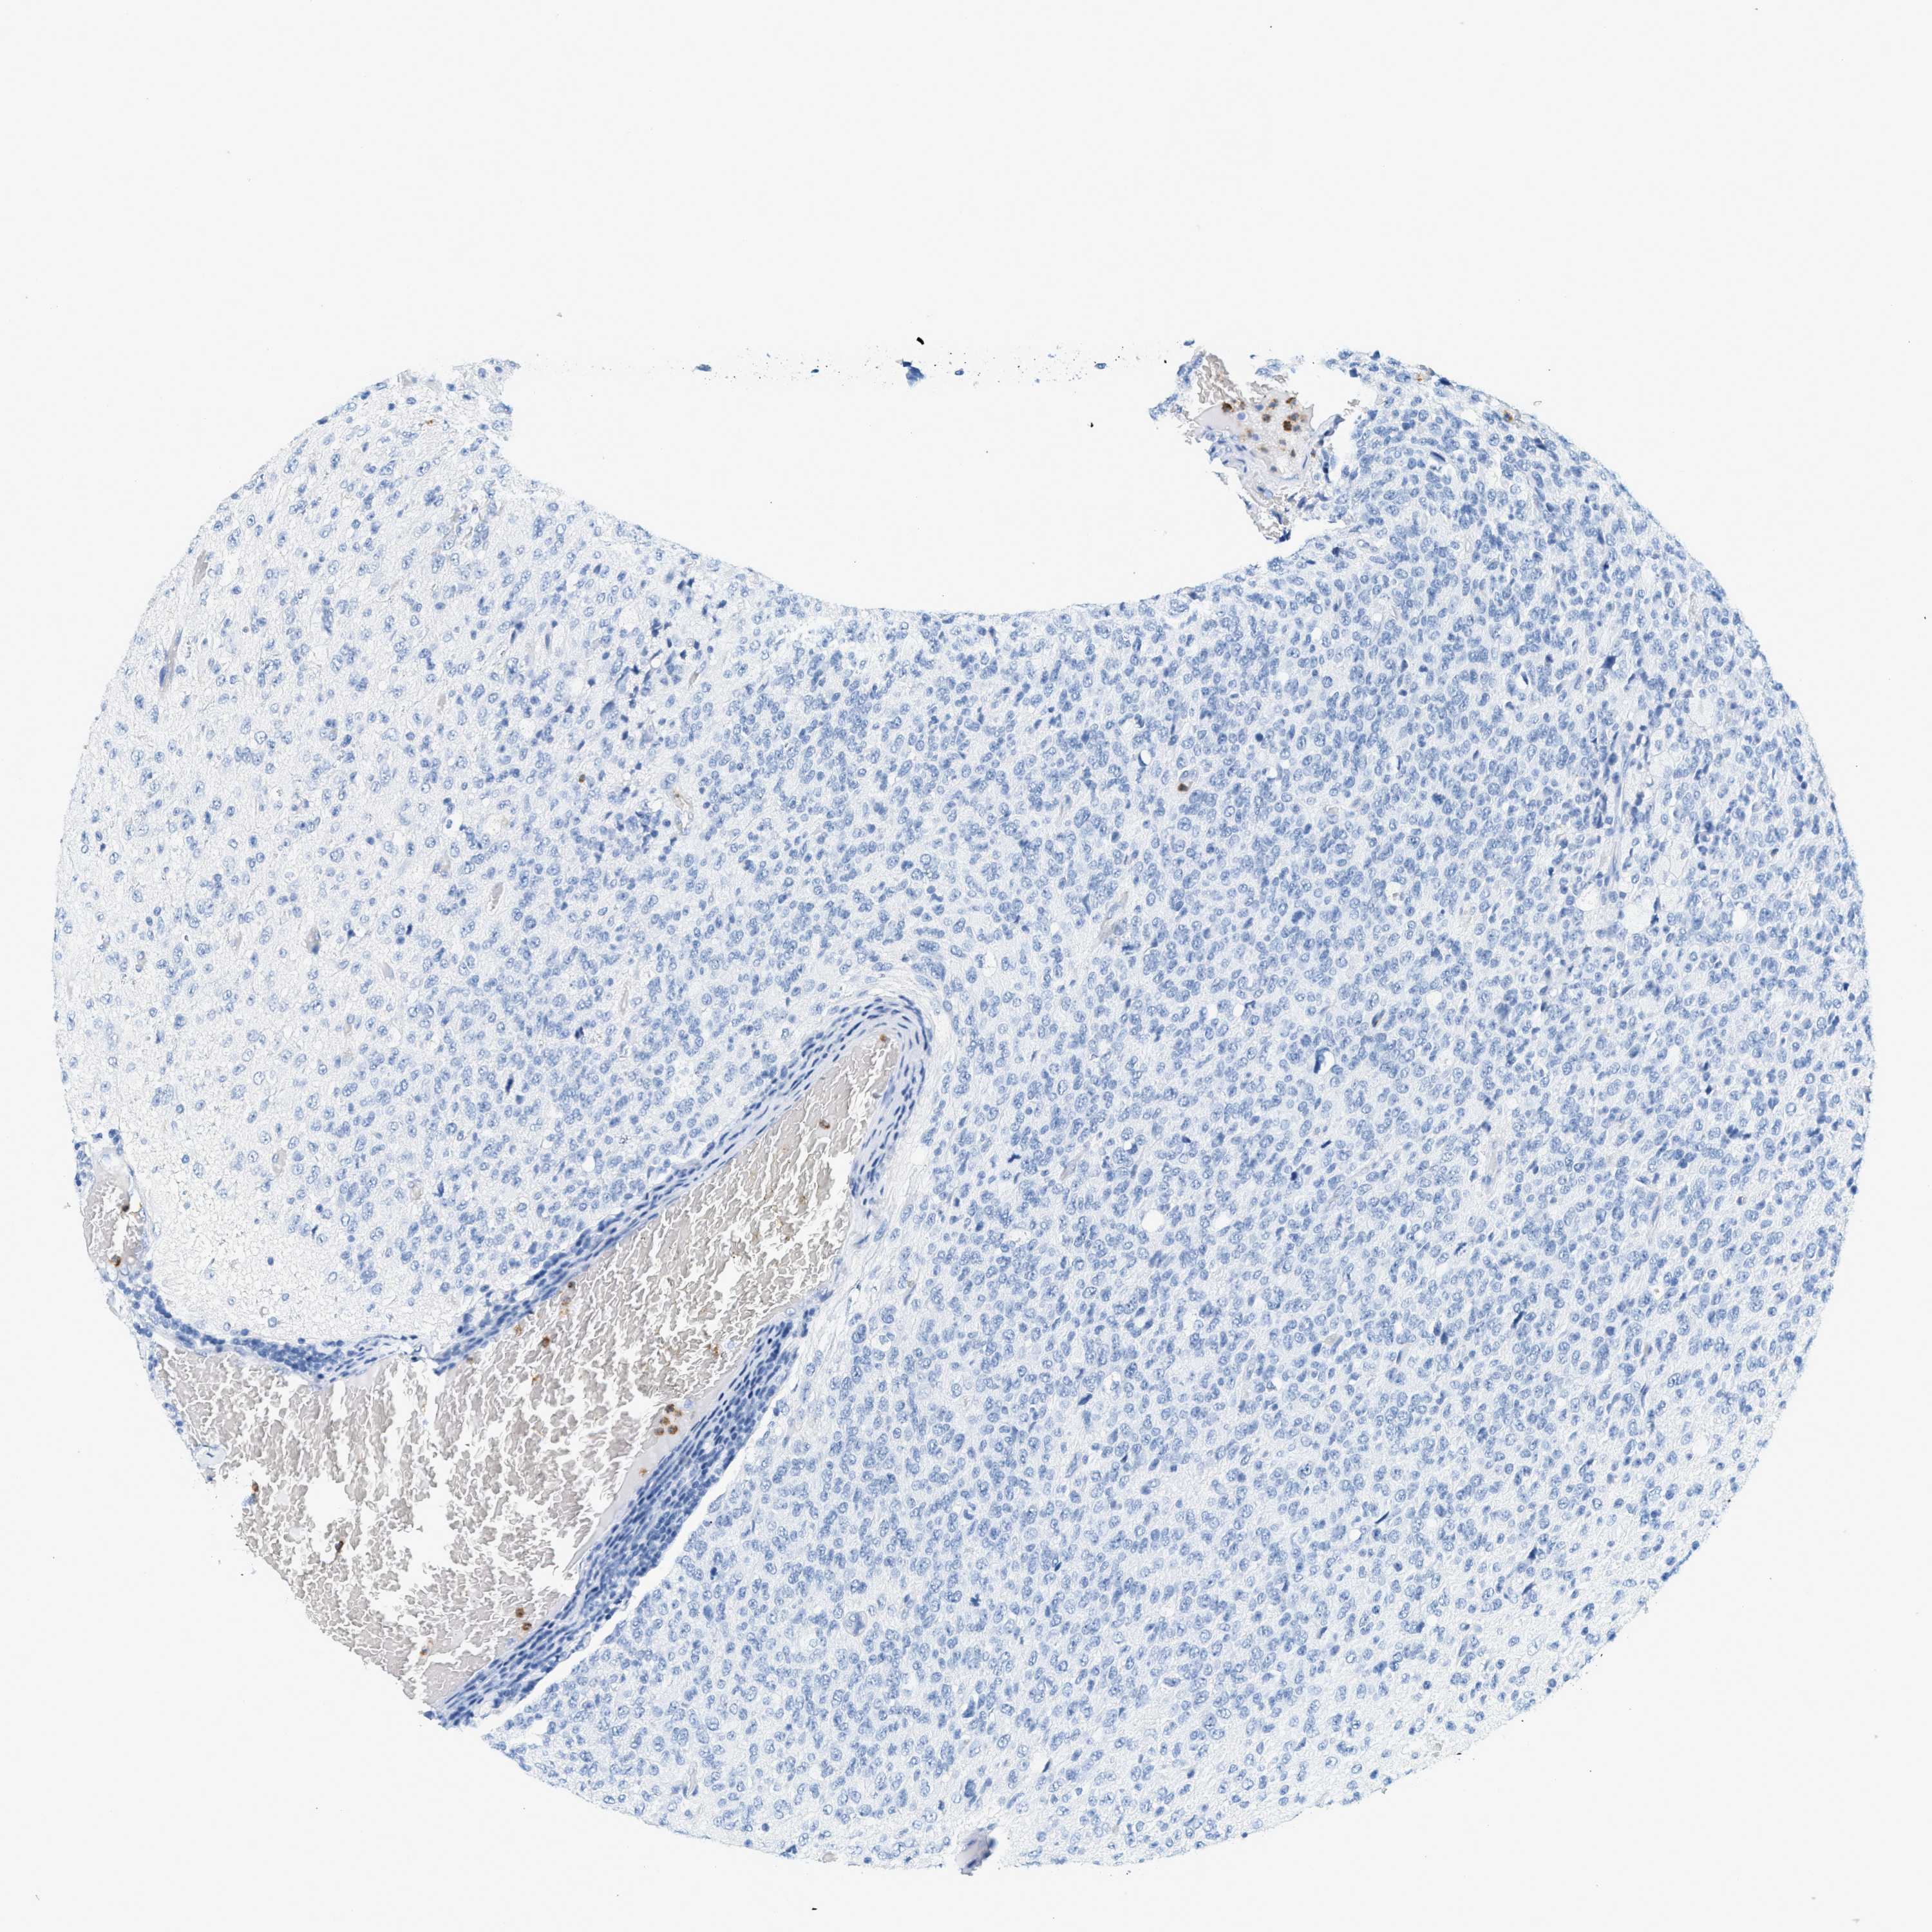

GLIOMA - Protein expressioni

A mouse-over function shows sample information and annotation data. Click on an image to view it in a full screen mode. Samples can be filtered based on level of antibody staining by selecting one or several of the following categories: high, medium, low and not detected. The assay and annotation is described here.

Note that samples used for immunohistochemistry by the Human Protein Atlas do not correspond to samples in the TCGA dataset.

Antibody stainingi

Antibody staining in the annotated cell types in the current human tissue is reported as not detected, low, medium, or high, based on conventional immunohistochemistry profiling in selected tissues. This score is based on the combination of the staining intensity and fraction of stained cells.

Each image is clickable and will lead to virtual microscopy that enables deeper exploration of all samples and also displays staining intensity scores, fraction scores and subcellular localization as well as patient and tissue information for each sample.

Antibody HPA002695

Antibody CAB016549

Antibody CAB016550

Glioma, malignant, High grade

Glioma, malignant, Low grade